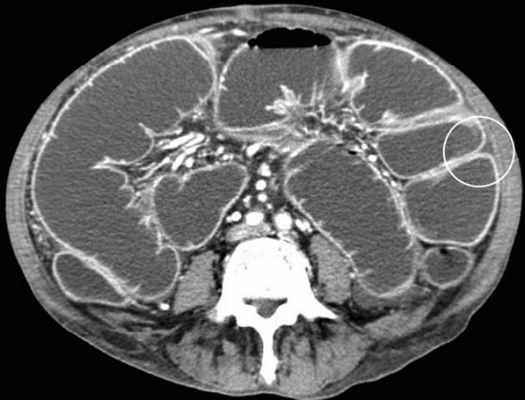

Основным методом окончательной, верифицированой диагностики непроходимости тонкой кишки на данный момент является СКТ/МДКТ с болюсным контрастным услением, являясь золотым стандартом визуализации.

КТ визуализация при простой форме

Хирургическая классификация тонкокишечной непроходимости также является основой классификации, используемой в радиологии. Раличают три формы:

- простая/компенсированная форма

-Расширенные петли тонкой кишки проксимальнее транзиторной зоны (зоны обструкции).

-Под транзиторной зоной надо понимать зонy кишки с очевидной разностью в диаметре просвета между расширенным проксимальным сегментом и местом сужения/обструкции. Визуализация этой зоны зависит от причины и механизма обструкции, а также от проекции расположения петли (аксиально, фронтально и т.д.). К сожалению, обнаружение этой зоны не всегда представляется возможным. При спаечном механизме или воспалении многими хорошо описан признак "птичьего клюва". При обструкции в результате алиментарного болюса транзиторная зона будет выглядеть как гетерогенное образование в просвете кишки без признаков контрастного усиления.

-Спавшиеся петли кишечника дистальнее уровня обструкции.

-Смешанный характер стаза содержимого кишечника в расширенных петлях. Некоторыми авторами описан "фекалоидный" тип стаза, описанный в литературе как "каловое содержимое тонкой кишки", в английской литературе-“small-bowel faeces sign”. Патогенез данного признака включает в себя много факторов:

замедление пассажа содержимого, нарушения механизмов абсорбции и секреции в тонкой кишке, рефлюкс из толстой кишки из-за недостаточности илео-цекального клапана, постановка желудочного зонда. Необходимо помнить, что этот признак неспецифичен при тонкокишечной непроходимости, его также можно определить на УЗИ и обзорной рентгенограмме брюшной полости.

-Нормальные неутолщённые стенки кишечника с гомогенным одинаковым контрастным усилением.

-В тощей кишке рисунок ворсинок слизистой (valvulae conniventes) тонкий, и он одинаково выглядят на всём протяжении.

-Отсутствие патологических изменений толстой кишки, толстая кишка как правило спавшаяся или содержит небольшое количество калового содержимого, распределённого по всему просвету.

-Отсутствие воспалительных изменений в брыжейке и внутрибрюшинном жире.

-Нормальная васкуляризация сосудов брыжейки.

-Отсутствие свободной жидкости в брюшной полости.

Различные КТ сканы при простой форме обструкции, cxематично изображены транзиторные зоны и спайки, которые как "хомут" или "удавка" как-бы душат петлю кишки.